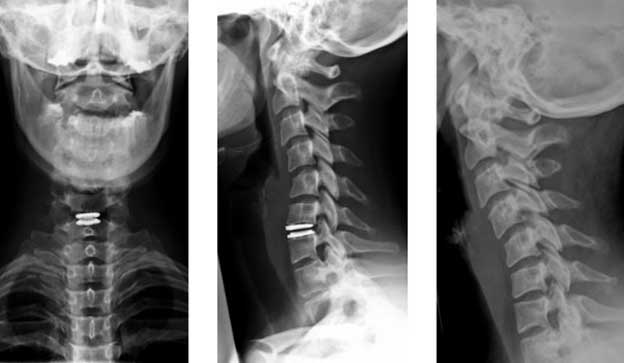

Рентген верхних позвонков является обязательным исследованием при шейном сколиозе. На рентгеновском снимке четко виден угол искривления, что помогает определить степень патологии. Рентгенологическое исследование назначается как на ранних, так и на поздних стадиях заболевания.

Компьютерная томография рекомендуется на поздних стадиях шейного сколиоза. Однако с появлением более современных методов, таких как МРТ, её использование стало менее распространенным. Магнитно-резонансная томография предоставляет детальную информацию о состоянии мягких тканей, нервных окончаниях и сосудах, что позволяет выявить и предотвратить возможные осложнения.

Хирургическое вмешательство направлено на устранение осложнений сколиоза и коррекцию положения позвонков. В самых тяжелых случаях может потребоваться замена позвонков.